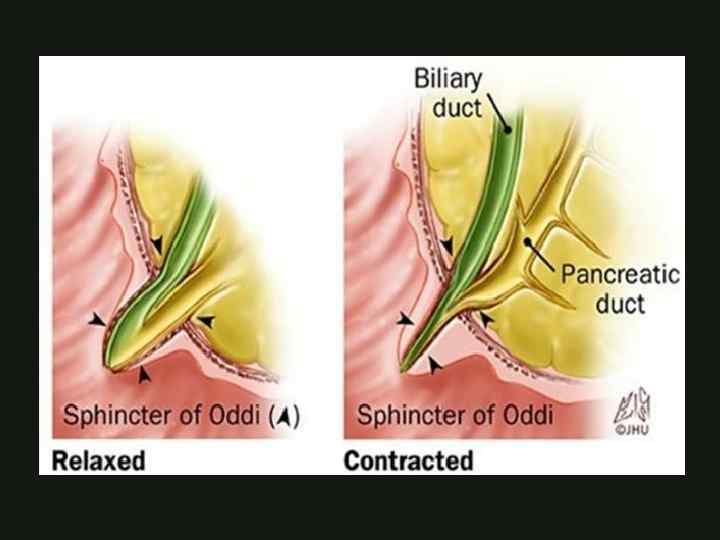

ЭМБРИОЛОГИЯ формируется на 4 неделе гестации из печёночного отростка вентральный зачаток формирует часть головки поджелудочной железы, крючковидный отросток и Вирсунгов проток КАФЕДРА ХИРУРГИИ МОСКОВСКОГО ФАКУЛЬТЕТА

ЭМБРИОЛОГИЯ формируется на 4 неделе гестации из печёночного отростка вентральный зачаток формирует часть головки поджелудочной железы, крючковидный отросток и Вирсунгов проток КАФЕДРА ХИРУРГИИ МОСКОВСКОГО ФАКУЛЬТЕТА

ЭМБРИОЛОГИЯ дорсальный зачаток формирует тело, хвост, часть головки поджелудочной железы и Санториниев проток на 37 день гестации формируется единый орган КАФЕДРА ХИРУРГИИ МОСКОВСКОГО ФАКУЛЬТЕТА

ЭМБРИОЛОГИЯ дорсальный зачаток формирует тело, хвост, часть головки поджелудочной железы и Санториниев проток на 37 день гестации формируется единый орган КАФЕДРА ХИРУРГИИ МОСКОВСКОГО ФАКУЛЬТЕТА